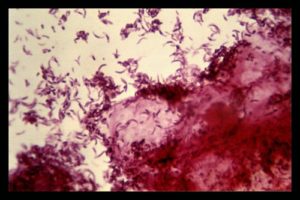

Энтеробактерии (лат.

enterobacteriaceae) — семейство грамотрицательных (как и другие протеобактерии) палочкообразные (бациллы), споронеобразующие бактерии, длиной 1-5 мкм, со жгутиками для передвижения.

Эти бактерии — факультативные анаэробы, расщепляют углеводы с образованием муравьиной кислоты и других конечных продуктов формиатного брожения. Некоторые из них могут разлагать лактозу.

Множество представителей семейства являются частью микрофлоры кишечника человека и животных. Они представляют большое число нормальной микрофлоры человеческого организма и значительное количество патогенных микробов: сальмонелла, кишечная палочка, чумная палочка и др.

Группа энтеробактерий включающая: сальмонеллы, шигеллы, эшерихии, клебсиеллы, собственно энтеробактер, серрации, протей, морганеллы, провиденции и иерсинии в норме обитают в желудочно-кишечном тракте человека, но при снижении защитных свойств слизистой кишечника, могут вызывать инфекции желудочно-кишечного тракта или других органов.